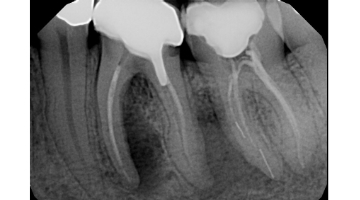

root canal canals tooth ray dental nerve treatment therapy infected rootcanal bacteria phoenix